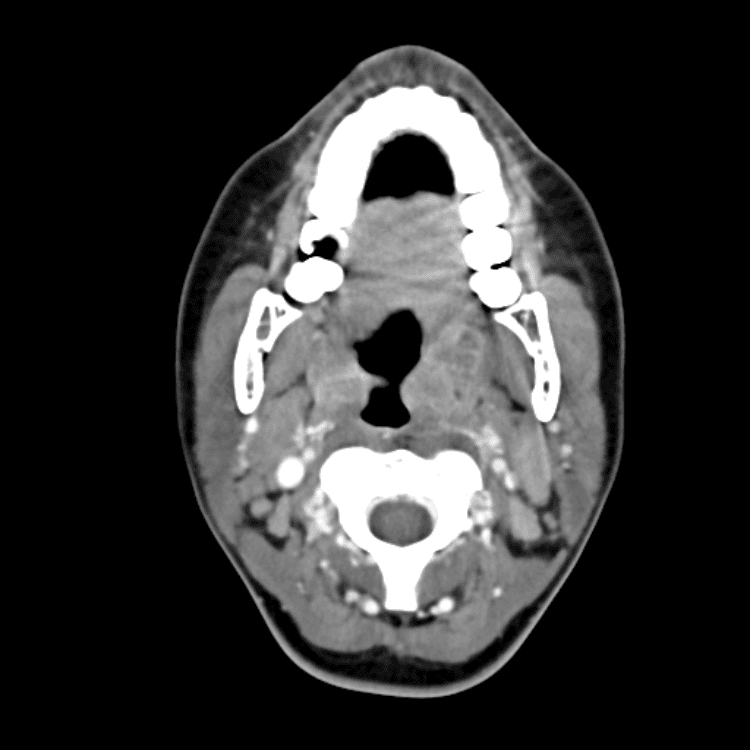

Head and Neck

Practice

Simulates call by including subtle or difficult cases and some normals.

27 cases